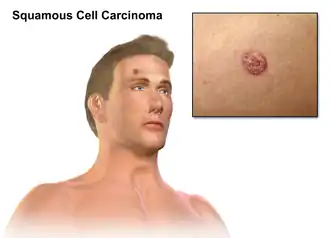

Cutaneous squamous-cell carcinoma

| Cutaneous squamous-cell carcinoma tends to arise from actinic keratoses (premalignant lesions); surface is usually scaly and often ulcerates (as shown here). | |

Cutaneous squamous-cell carcinoma (cSCC), also known as squamous-cell carcinoma of the skin or squamous-cell skin cancer, is one of the three principal types of skin cancer, alongside basal-cell carcinoma and melanoma.[10] cSCC typically presents as a hard lump with a scaly surface, though it may also present as an ulcer.[1] Onset and development often occurs over several months.[4]

SCC of the skin begins as a small nodule, and as it enlarges, the center becomes necrotic and sloughs, and the nodule turns into an ulcer, generally developing from an actinic keratosis. Once keratinocytes begin to grow uncontrollably, they have the potential to become cancerous and produce cutaneous squamous-cell carcinoma.[22]